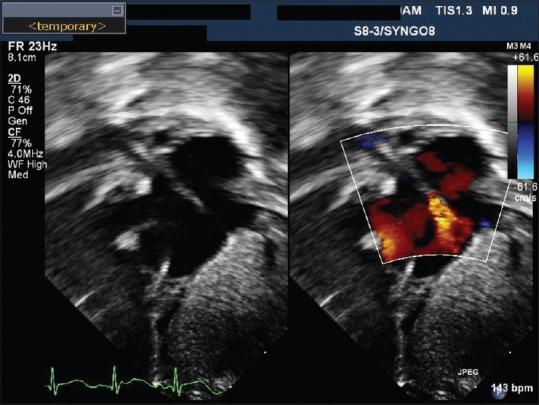

Retained intravascular foreign body is a well-known complication of central venous access placement in children as well as adults. Most of these foreign bodies are radio-opaque and hence are removed under fluoroscopy guidance. In our case, we describe the removal of an intracardiac radiolucent foreign body in an infant utilizing a combination technique - transesophageal echocardiogram and fluoroscopy.

血管内异物残留是儿童及成人中心静脉置管的一种常见并发症。这些异物大多是不透射线的,因此在荧光透视引导下取出。在我们的病例中,我们描述了采用经食管超声心动图和荧光透视联合技术为一名婴儿取出心内透射线异物的过程。